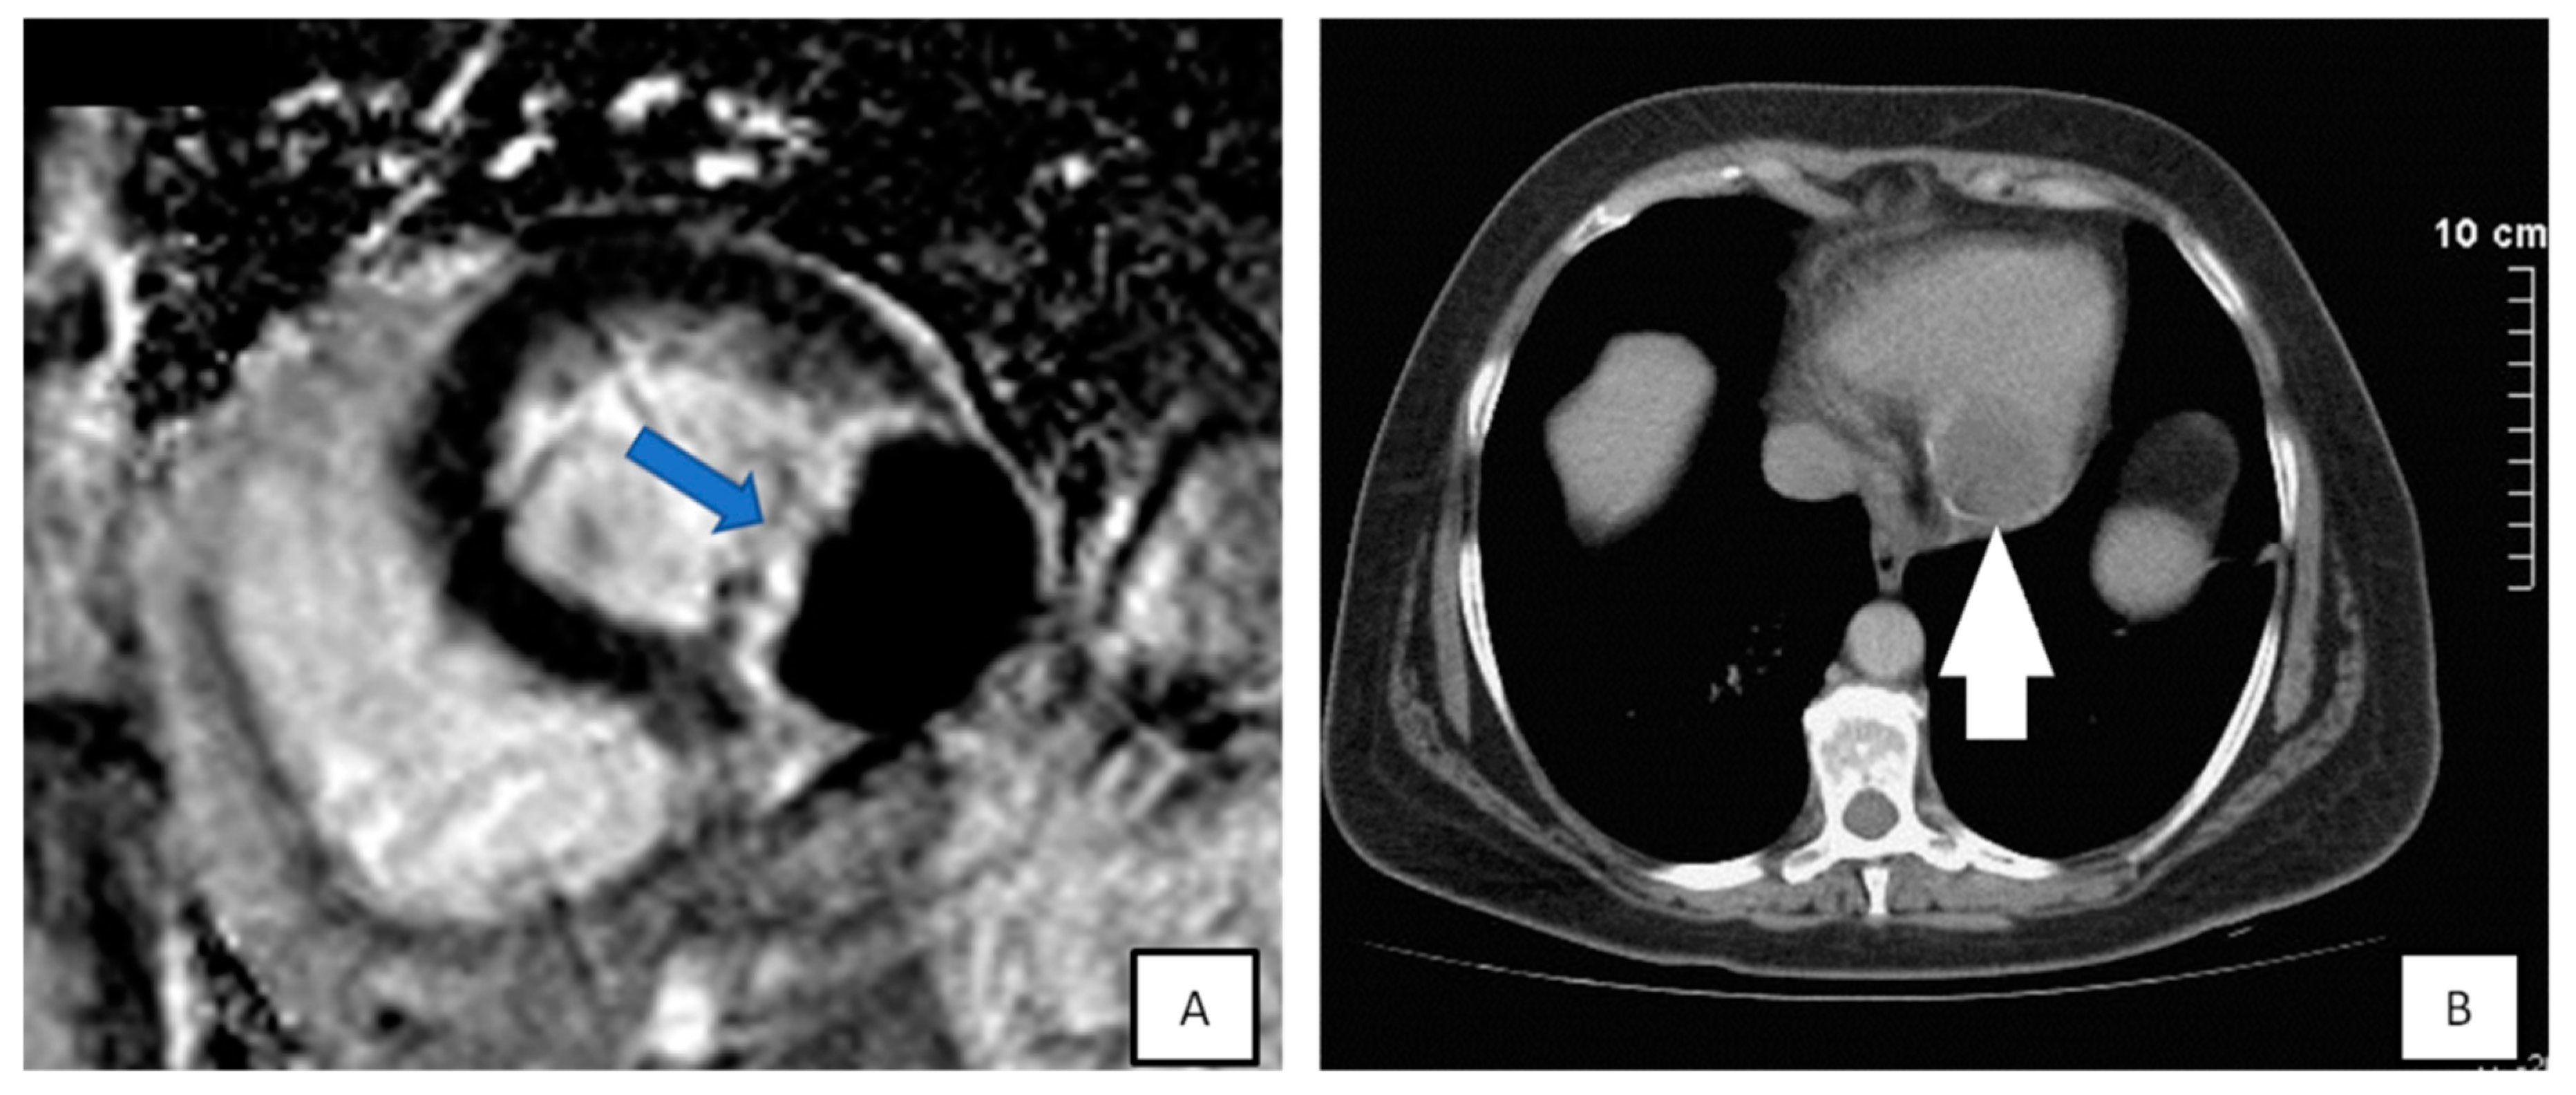

3.4. Cardiac Magnetic Resonance

- Early gadolinium enhancement (EGE) which identifies thrombus from the adjacent hypokinetic cardiac wall.

- Late gadolinium enhancement (LGE) that is ideal for fibrosis and necrosis identification.